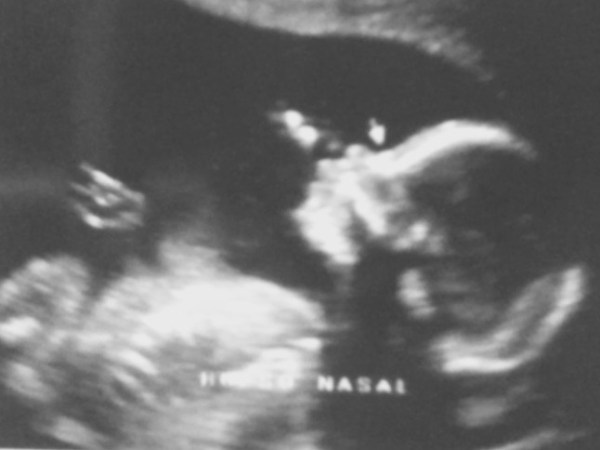

En febrero de 2013 nació Luciano y con él, un nuevo y desconocido mundo. Un amor y una entrega incomparables. Una vida distinta llena de primeras veces, de aprendizajes, de babear con cada cosa que hacía… y también agotadora, pues sin que en ese momento lo supiera, era un bebé de alta demanda. Leer más

Mi marido y yo teníamos claro que queríamos tener un hijo. También teníamos claro que queríamos prepararnos de…